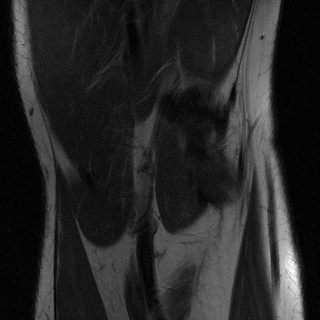

Accelerated MRI enhancement: The FastMRI [3] database consists of more than 1500 multi-coil diagnostic knee MRI scans and corresponding emulated single-coil data. Our experiments are based on a subset of nearly 800 coronal proton-density weighted scans without fat-suppression from the official train and validation single-coil releases. We remove of the patients for evaluation and split the remaining patients into input and target data. While the target domain consists of slices from fully-sampled MRI scans, we consider 4x acceleration (only of k-space measurements) for the slices by using the subsampling scheme discussed in [3, 4]. This yields 7.1k train slices for input and 6.9k for target. We are aware that enhancement of accelerated MRI can also be considered as a supervised task since generation of paired instances is feasible. However, this experiment should demonstrate possible applicability of the proposed framework to inverse problems in general.

In Table 2 we observe for the accelerated MRI enhancement task on FastMRI that our method UAPI significantly outperforms other benchmark on unaffected test data but gives modest accuracy when additional noise and perturbed pixels are added. Figure 4 shows the superior performance of CUT in terms of the PSNR metric for noisy data. This is quite interesting since that has not been the case for the previous modality propagation application. The task of accelerated MRI enhancement strongly differs from the other two applications. While the goal of modality propagation and MRI-to-CT synthesis is to come up with a completely new image, the aim of accelerated MRI enhancement is to improve quality of a already existing image. In fact, the methods cycleGAN, UGAC, gcGAN, PI and UAPI depend on a rather simple U-Net [34] implementation and a standard DCGAN critic [35] with the aim to demonstrate plausibility of different transfer approaches on easy-to-implement frameworks. The CUT method is a benchmark where the publicly available source code had to be used, consisting of a ResNet-based generator [11] and built-in data augmentation techniques that may better compensate for noisy input data. Nevertheless, our methods PI and UAPI seemingly achieve better results compared to the U-Net based benchmarks. We will take up investigation of robustness of our methods in combination with different network architectures as a future goal.

4.4 Qualitative Evaluation

In Figure 5 we analyze the prediction quality of our and compared approaches in a qualitative way. Considering modality propagation in MRI, we see that usage of uncertainty-aware patch invariance (UAPI) gives a better detailed weighting of the cerebrospinal fluid in the middle of the brain. In general, employing patch invariance yields better preservation of fine structures. This observation also applies to accelerated MRI enhancement. In particular, CUT and UAPI provide comparatively sharper knee images with more high-frequency details than the other methods.

Additional to improved accuracy we demonstrate the efficacy of estimating the scale maps with the proposed method. The input-dependent non-negative scale maps are derived from the second output branch , see (9). Indeed, the predicted scale maps are able to model uncertainty inherent from data. This can be observed in Figure 8, where in addition to the transferred images also the predicted scale maps and the absolute residuals between predicted and ground truth images are displayed. Obviously, uncertainty is relatively greater in regions with higher residual values. From the scale maps it can be deduced for which positions the generator is comparatively uncertain in its prediction, such as the cerebral cortex and eye sockets in head MRI or the lateral knee ligaments in knee MRI.